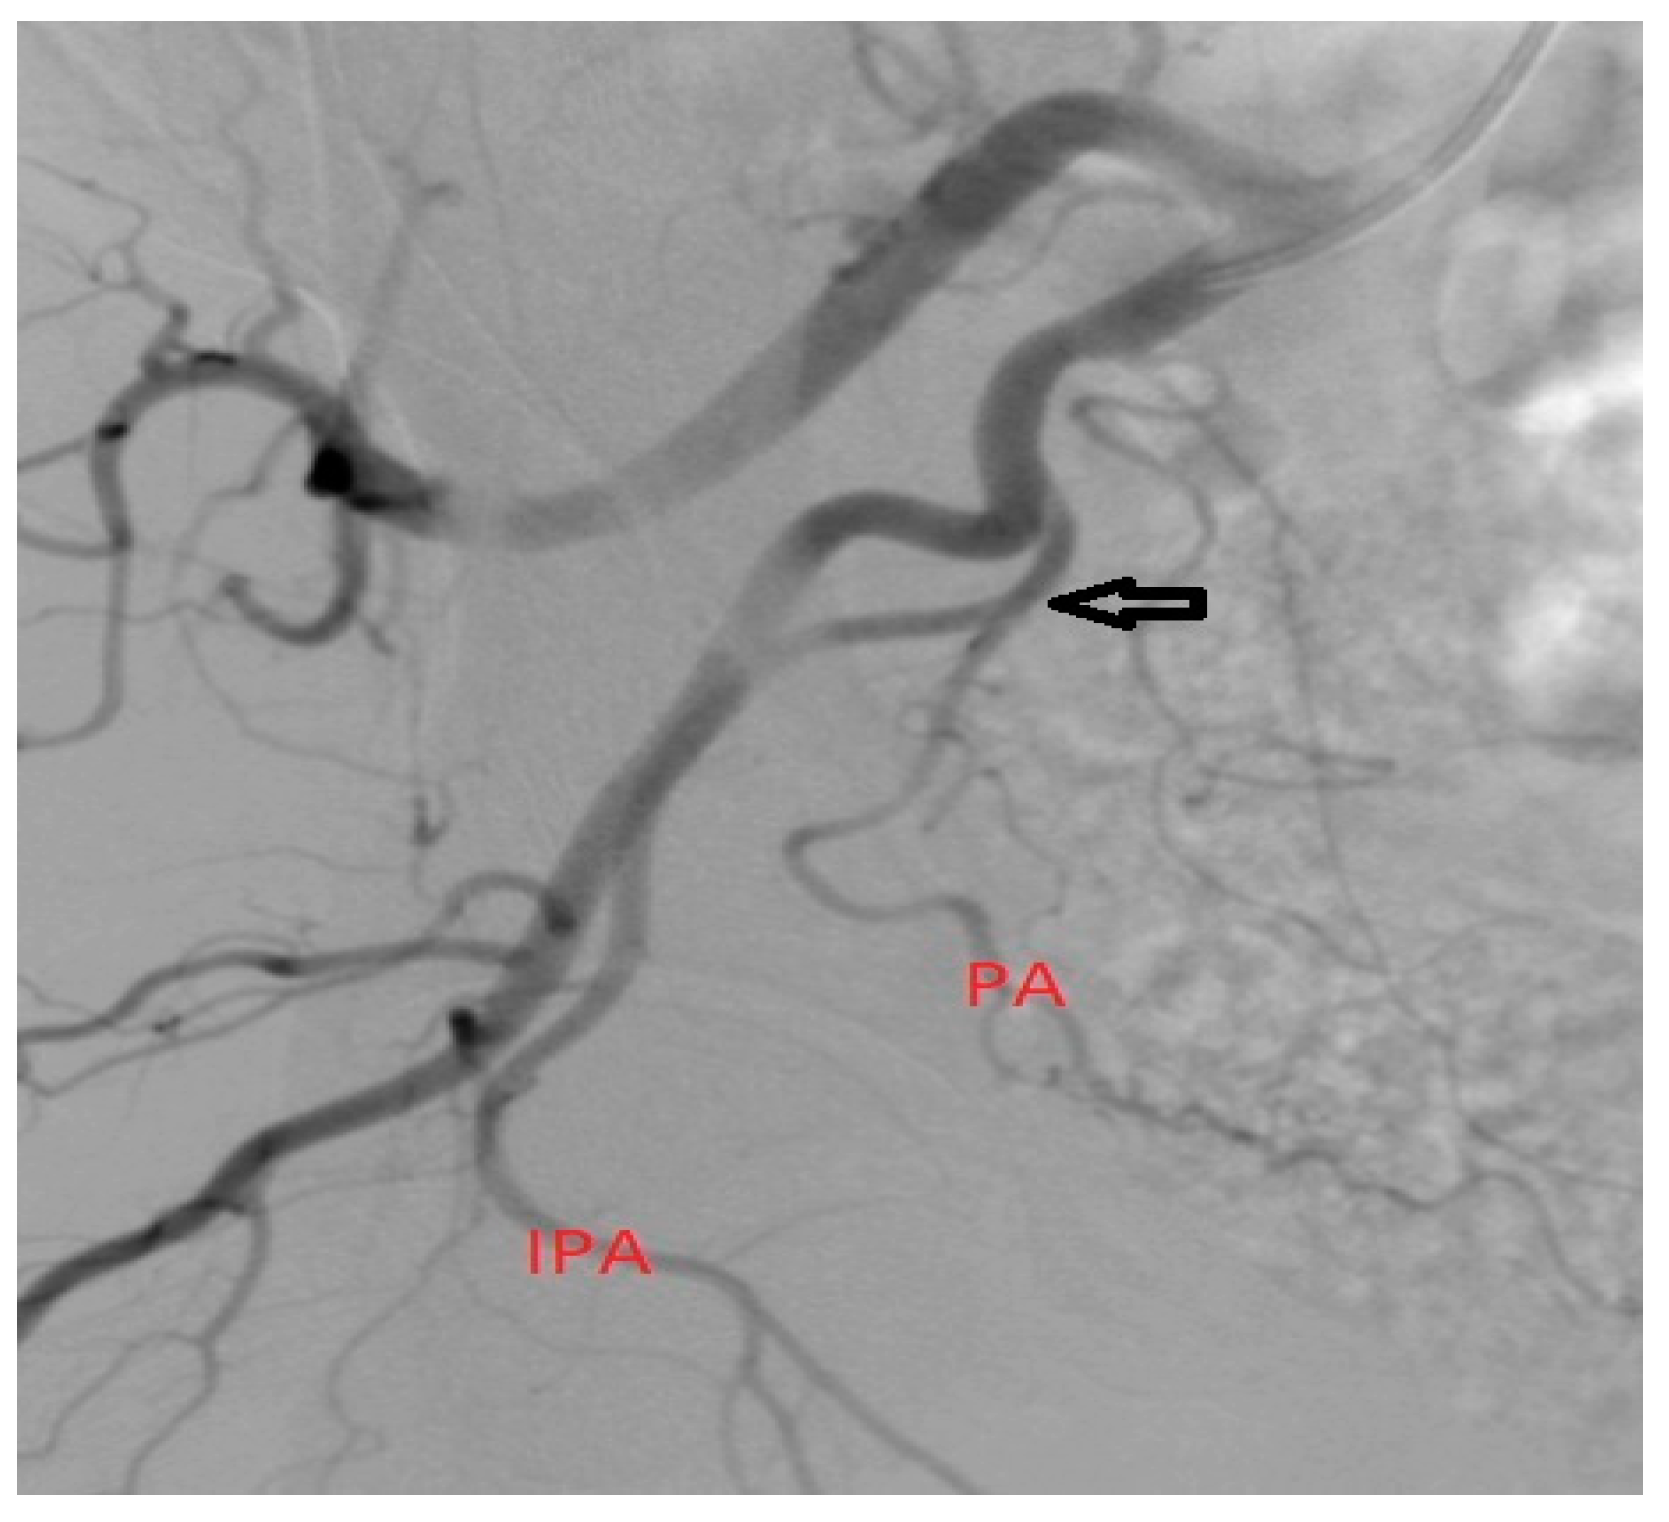

- There are cases when we can identify IPA and IPA accessories, which must not be confused with the PA. At the level of accessory IPAs, we can find the origin of the middle rectal artery, which has a characteristic pattern of enhancement that cannot be mistaken with the prostatic blush [12] (Figure 2);